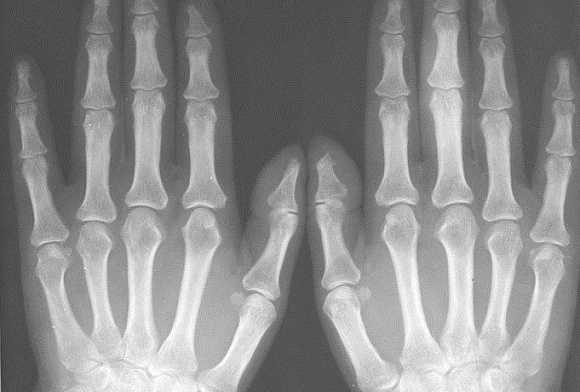

- Прямая проекция. Для такой съёмки кисть укладывается горизонтально, на стол - тыльной стороной или ладонью. Лучи рентгена будут проходить через кисть перпендикулярно кассете с плёнкой. На таком снимке будут определяться все кости запястья, за исключением гороховидной. Также будут видны лучезапястный сустав, пястные кости, запястно-пястные суставы, межзапястный сустав и фаланги пальцев.

Также хотелось обратить внимание на неправильно выбираемую зону обследования. Например, зачастую при наличии односторонних клинических изменений в одном пястно-фаланговом или плюсне-фаланговом суставе врачи ограничиваются рентгенографией исключительно этой области. Однако, именно характер патологических изменений в обеих кистях, их локализация и распространённость, анализ того какие группы суставов изменяются в самом начале заболевания должны обязательно учитываться при оценке рентгенограмм для того, чтобы правильно интерпретировать полученные данные и провести дифференциальный диагноз между различными ревматическими заболеваниями. Поэтому в ревматологической практике для уточнения диагноза необходимо проводить по показаниям либо прямую сравнительную рентгенограмму кистей с захватом лучезапястных суставов либо прямую сравнительную рентгенограмму стоп.

Исходя из нашего опыта, результаты рентгенографии нередко могут зависеть от техники и правильного позиционирования объекта съемки. В настоящее время требованием всех протоколов исследований является соблюдение максимально унифицированных условий проведения рентгенограмм кистей и стоп. Так для общей оценки поражения суставов необходимо снимать обе кисти или стопы на одной пленке, обязателен захват лучезапястного сустава. Требования к расположению пациента при рентгенографии кистей и стоп изложены в соответствующих руководствах по рентгенологии. Врачу общей практики при направлении к рентгенологу обязательно необходимо указывать, что больной направляется на сравнительную рентгенограмму кистей в прямой проекции с захватом лучезапястных суставов или на прямую сравнительную рентгенограмму стоп.